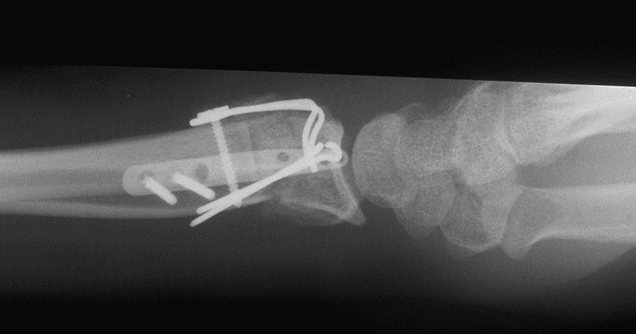

Case 2 Postop